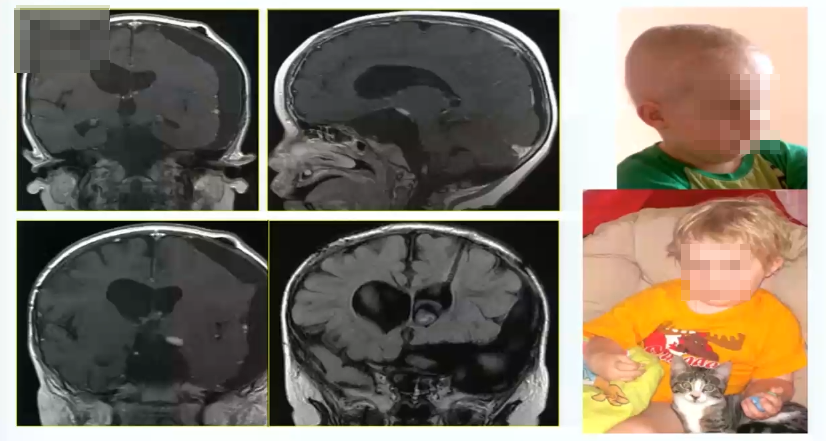

视路胶质瘤全切手术病例1:

2岁男孩,毛状黏液样星形细胞瘤2级,严重的左侧视觉障碍,肿瘤较大

术中情况:采取眶颧入路,肿瘤大,累及向上向下,需要宽广的视野。

术后情况:肿瘤全切,术后一年,孩子状态良好。小儿肿瘤放化疗专家为其进行后续治疗。